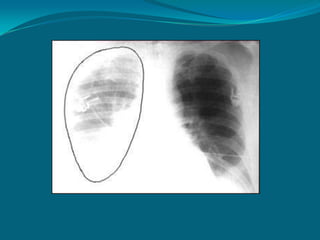

NEUMOTÓRAX

 Se define como la

presencia de aire en la

cavidad pleural

 Un neumotórax grande se

reconoce con facilidad por

que el pulmón colapsa

totalmente:

 La imagen es densa

 No hay trama vascular en

el pulmón afectado